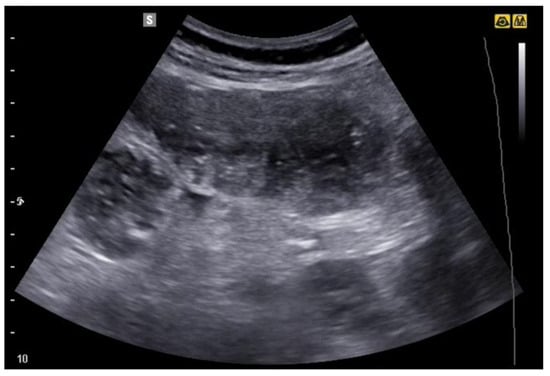

6. Bowel Obstruction

6.1. GIUS Signs of SBO

6.2. GIUS Signs of LBO